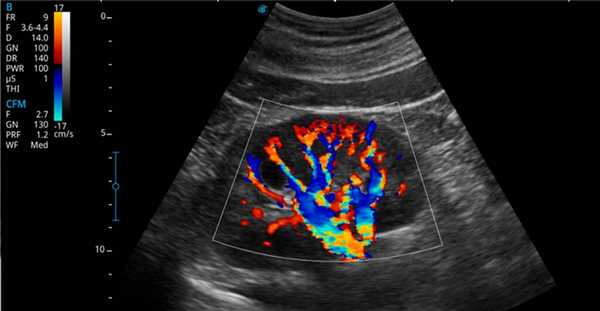

Рис. 3. Сосуды печени в режиме цветного картирования.

- цветной метод позволяет получить пространственные реконструкции объемных изображений с включением данных цветного допплеровского сканирования или сосудистого режима (рис. 3).